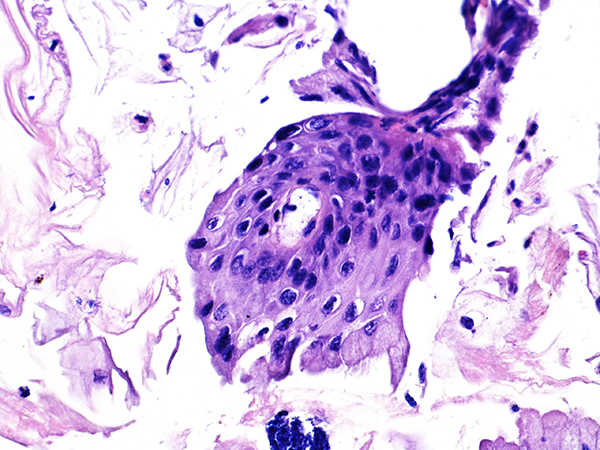

Case 3

Soft Bx CIN 3

40x - High Power |